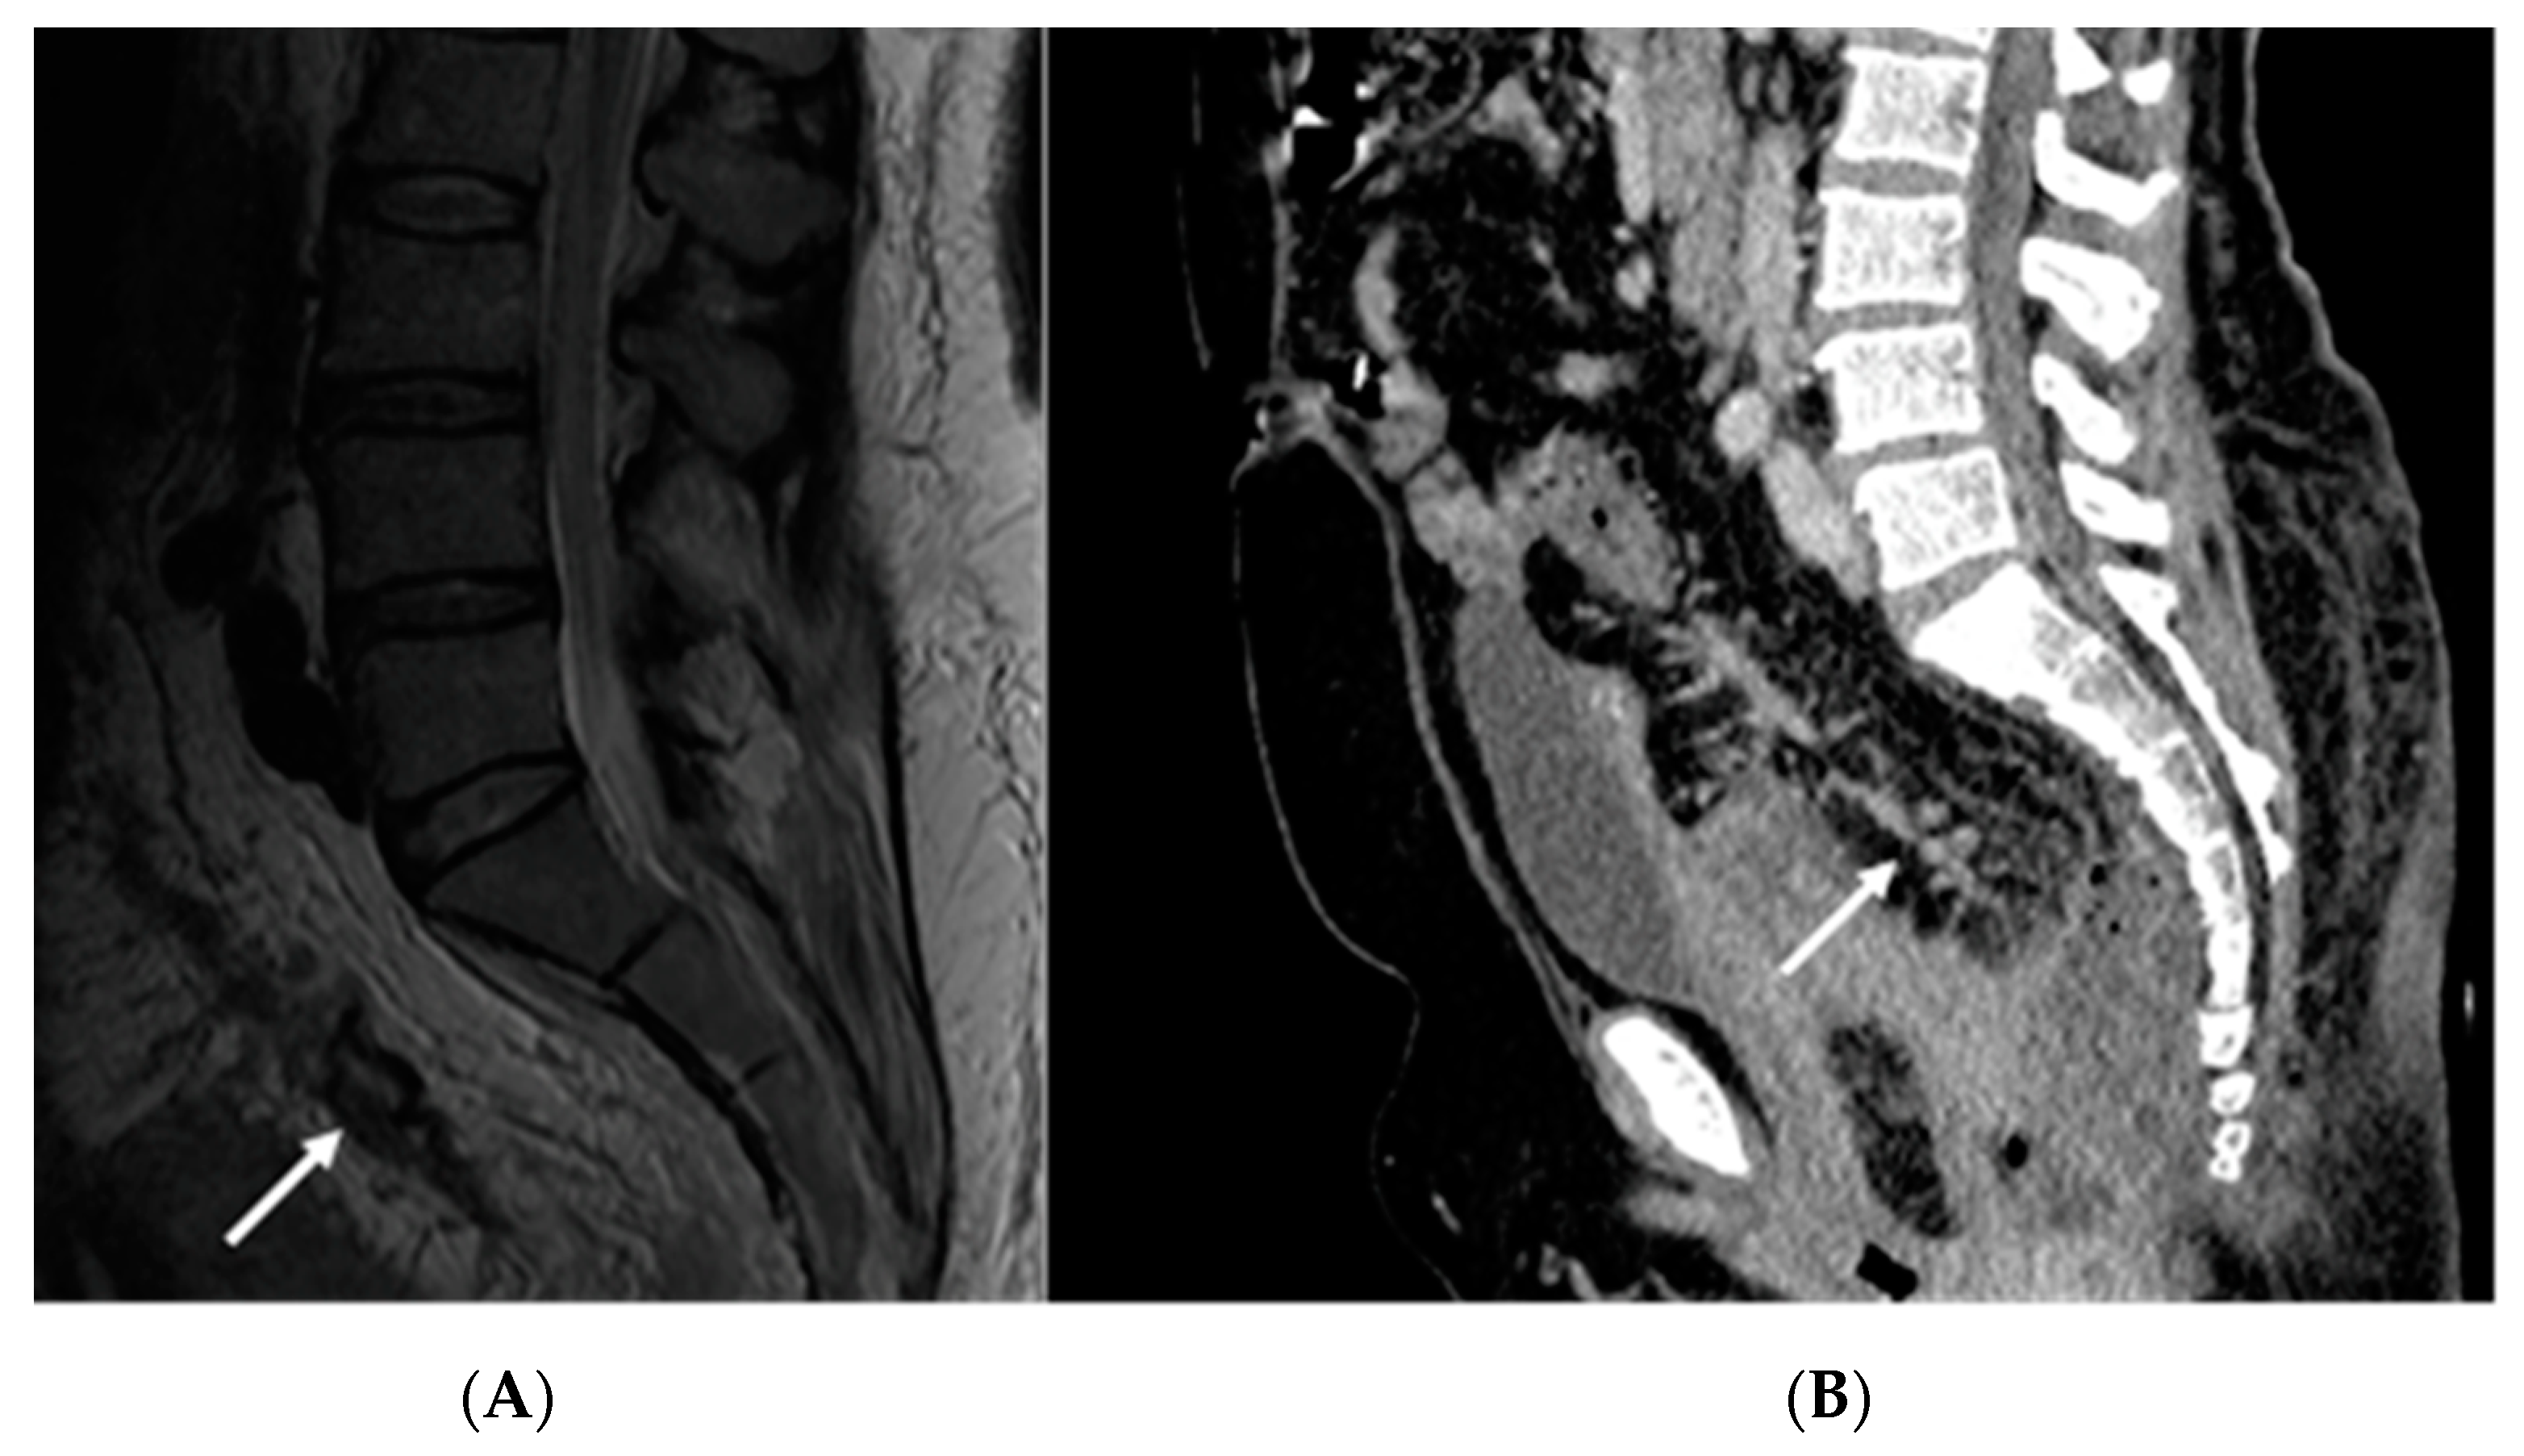

2.1. Case Report